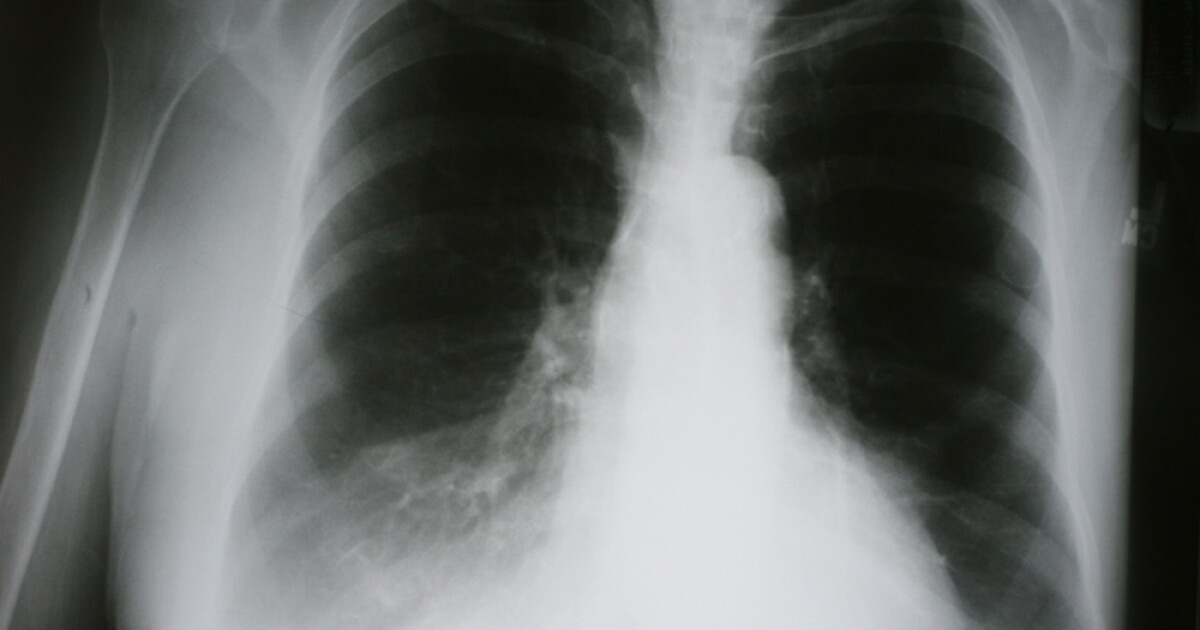

Smoking X Ray . However, each person is not the same, because smoking time is different smoking dose, so the impact of tobacco on the lungs is different. But basically the symptoms are the same, just different in degree. The classic finding on a smoker's chest film is increased lung volume, which in turn is caused by. Smoking can change the physical appearance of the lungs. Read about smokers' lungs, and see pictures, graphics, and illustrations of diseased lung tissue from smoking. The chart below summarizes some common. Smoking can result in chronic bronchitis, emphysema, lung cancer, and copd.

Read about smokers' lungs, and see pictures, graphics, and illustrations of diseased lung tissue from smoking. Smoking can result in chronic bronchitis, emphysema, lung cancer, and copd. The chart below summarizes some common. Smoking can change the physical appearance of the lungs. The classic finding on a smoker's chest film is increased lung volume, which in turn is caused by. However, each person is not the same, because smoking time is different smoking dose, so the impact of tobacco on the lungs is different. But basically the symptoms are the same, just different in degree.